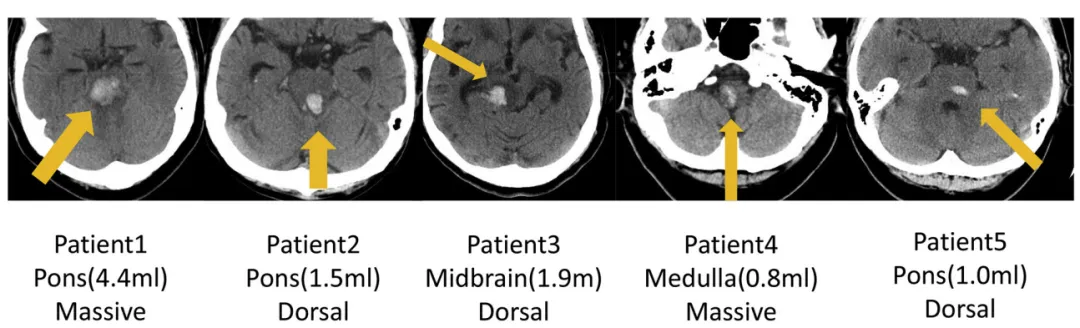

INC巴特朗菲教授2018年发表论文《Surgical Treatment for Primary Brainstem Hemorrhage to Improve Postoperative Functional Outcomes》讨论5例接受手术治疗的原发性脑干出血患者,分析手术治疗改善术后功能结局的能力。研究显示术后1周功能结局(表3)和出院后6个月改良Rankin量表评分(表4)均获改善。

5例原发性脑干出血(PBH)患者轴位CT影像。

表4:手术前与术后6个月Rankin量表评分对比。